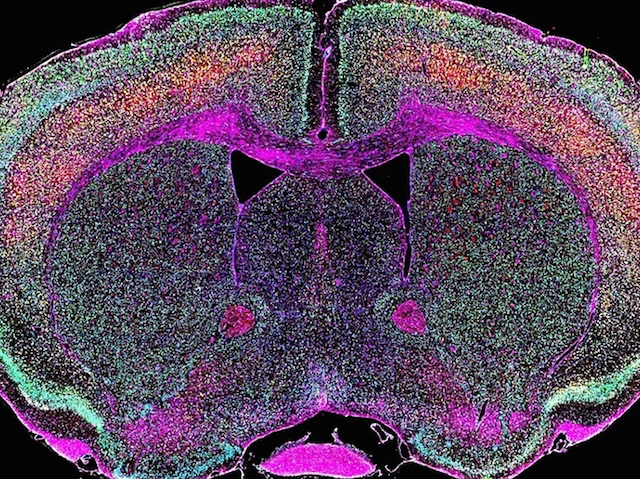

Up to 8% of our DNA comes from viruses whose genetic codes spliced themselves into our ancestors’ genomes during infections that took place over thousands of years. While most of it's usually harmless junk, researchers have recently found that a deadly motor neuron disease known as amyotrophic lateral sclerosis (ALS) could be triggered when ancient viral genes called HERV-K are roused from their millennial slumber. This set of genes, stained yellow in this slice through the cerebral cortex of a mouse, were found to have been activated in a group patients who had died of ALS, the researchers discovered, where they produced a protein toxic to nerve cells. While ALS has been linked to mutations in over 50 different genes, what caused these viral genes to switch back on remains a mystery that the scientists now want to solve to neutralise them.